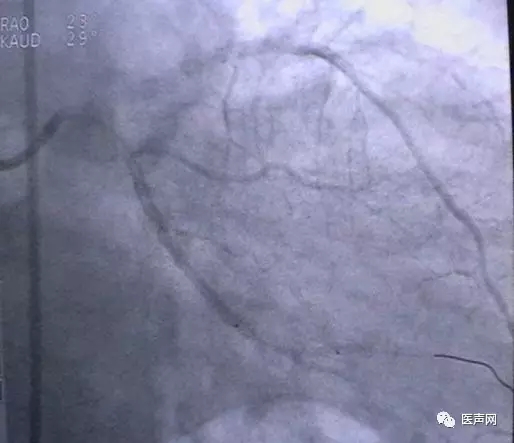

病例1: 冠脉搭桥术后,静脉桥CTO(CABG, VB-CTO)

箭头所示为第3个吻合点

(pre-PCI)

VB-对角支(jump)---LCX(jump)-PDA远端,第一个吻合以下完全阻断。

当打通后,发生室速,电复律---出现无复流---室速---植入支架(TAXUS Liberte)

当导引导管非常深置(very very deep seating)时,你可以想象支持力有多大,永远不要忘记他做RCA-CTO时导引导管深插到RCA中段的例子。此病例实际上PDA未能开通,在6月28日 Dr. Lauer终于用类似方法打通了PDA。